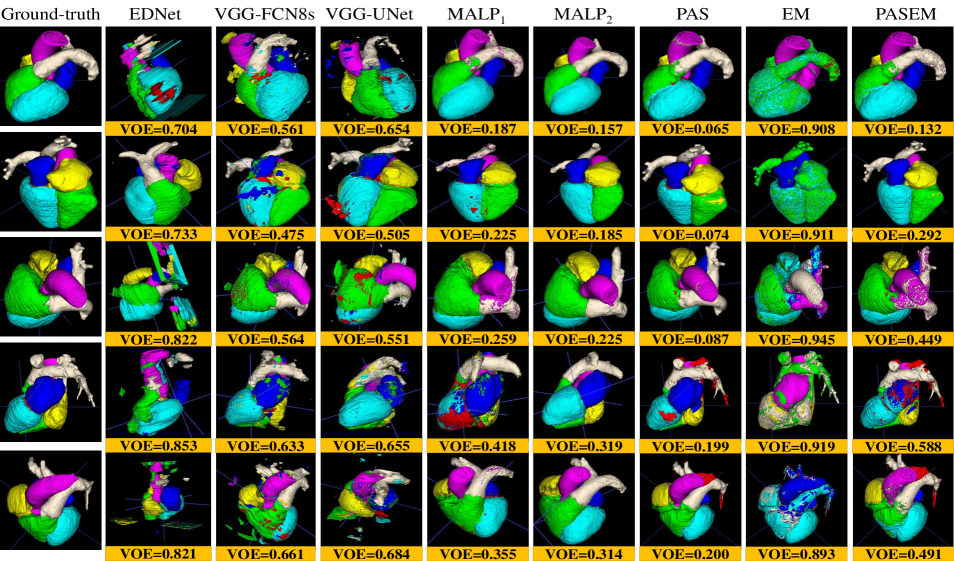

Fig. 7 exhibits the Box and Whisker visualization of all the methods showing the spreads and centers of the DSC, VOE, and Sn metrics for all the 20 test images, either CT or MRI scans.

Fig. 8 (a) and Fig. 8 (b) display the qualitative segmentation results for both the CT (top) and MRI (bottom), respectively, from all the methods.

The experimental results in Table III quantitatively demonstrate that the EDNet is the worst-performing method than the other two CNN-based methods, such as VGG-UNet and VGG-FCN8s, by the margins of and for CT scans and and for MRI scans, respectively, concerning the mDSC. Those two networks also defeat the EDNet for the other two metrics (mVOE and mSn) with significant margins (see in Table III). Although those three networks have the same number of convolutional and pooling layers in the encoder and decoder, they constructionally vary in skip connection employment (see details in subsection II-C). The results on both the imaging modalities reveal that the appliance of skip connection has outputted better-segmented substructures, as the local information from the shallower layers is utilized to reconstruct output masks through the skip connection (see the results in Table III). Again, it is seen from Fig. 7 that the DSC, VOE, and Sn from the EDNet are sparse for both the CT and MRI scans, with significantly fewer median metrics, which demonstrates that EDNet produces scattered results for each of the testing cases. On the other hand, the upper- and lower-whisker for all three metrics are closer for VGG-FCN8s and VGG-UNet than the EDNet (see in Fig. 7), which shows better-robustness of them comparing the EDNet.

Furthermore, the qualitative results in Fig. 8 depict that both the VGG-UNet and VGG-FCN8s provide better-segmented substructures of both the modalities (CT and MRI) than the EDNet. In some examples of the EDNet, none of the target substructures are segmented, which provide VOE as (see upper-whisker in Fig. 7 (b)). The encoders in all three networks have 13-convolutional and 5-pooling layers, where the in-depth features obtained from them have lost spatial location information due to pooling in the encoders. Hence, the output masks from EDNet have less local information, which is solved in the VGG-UNet and VGG-FCN8s due to the concatenation of local information through the skip connection, providing an alternative path for the gradient with backpropagation. It is experimentally validated in our investigations that the additional skipping paths are beneficial for improving the segmentation results of different heart substructures.

III-A2 Results for MALP-based methods

The label propagated segmentation results utilizing different deformed atlas images are quantitatively and qualitatively manifested in Table III, Fig. 7, and Fig. 8. The median and MVF schemes of level propagation, as described in subsection II-B2, generate the heart segmentation results with the mVOEs of and , respectively, for CT scans and and , respectively, for MRI scans. Table III demonstrates that the MVF scheme outperforms the median method of MALP by the margins of and respectively for CT and MRI modalities for mDSC. The former MALP method also outperforms the latter MALP method with significant margins concerning the other two metrics (mVOE and mSn). The Box and Whisker visualization of all three metrics in Fig. 7 for both the methods demonstrate the superiority of the MVF scheme than the median strategy for both the imaging modalities. Fig. 8 (top) and Fig. 8 (bottom) exhibit the qualitative results respectively for CT and MRI scans for both the median (MALP1) and MVF (MALP2) schemes. Those results qualitatively confirm that the segmented substructures from MALP1 suffer from the outliers (see in fifth and sixth columns of Fig. 8), where most of the organs are erroneously labeled with other organs. All the experimental results reveal that the MVF scheme has better dealt with the outliers as it counts the majority of the labels from the voting candidates, whereas the median method estimates the median values of the counter, which may not be matched by the majority voters.

III-A3 Results for probabilistic atlas-based methods

The WHS results of the probabilistic atlas are exhibited in Table III, Fig. 7, and Fig. 8, where we employ our three methods, such as PAS, EM, and PAS+EM (see details in subsection II-B2). The PAS, EM, and PAS+EM schemes of probabilistic atlas provide the heart segmentation results with the mVOEs of , , and , respectively, for CT scans and , , and , respectively, for MRI scans. Table III exhibit that the PAS scheme exceeds the other two methods, such as EM and PAS+EM, by the margins of and for CT scans concerning the mDSC, respectively, whereas it also beats them by the margins of and for MRI scans, respectively, in terms of the mDSC. Similarly, the EM and EM+PAS are also defeated by the proposed PAS method for mVOE and mSn for both the chest imaging modalities with considerable margins (see in Table III). The spreads and centers of the DSC, VOE, and Sn metrics for all the 20 test images (either CT or MRI scans), as exhibited in Fig. 7, also reveal the supremacy of the proposed PAS method over the other two methods (EM and EM+PAS).

However, incorporating the PAS algorithm with an EM algorithm extends the WHS outcomes by the margins of and in terms of mDSC respectively for CT and MRI modalities. Still, the PAS technique is a defeating method. Again, Fig. 8 (top) and Fig. 8 (bottom) show the qualitative WHS outcomes for the CT and MRI scans for the PAS, EM, and PAS+EM designs, respectively. Those results show that the segmented substructures from EM and PAS+EM yield the outliers substructures (see in eight and ninth columns of Fig. 8), where the EM results suffer severely by the outliers. The embodiment of PAS with the EM has significantly reduced the outlier effect from the WHS results of the EM technique, as qualitatively depicted in Fig. 8.